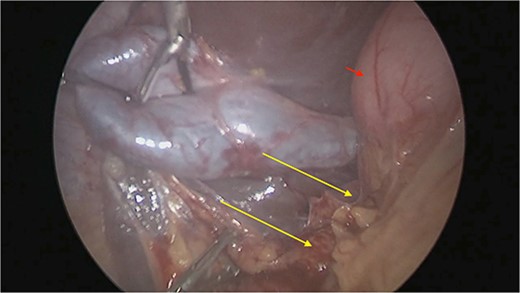

There were extensive perihepatic adhesions with involvement of the subhepatic space (Fig. 3). The initial intraoperative assessment was that this inflammation was secondary to a prior cholecystitis, but subsequent dissection revealed a pristine gallbladder (Fig. 4) with inflammatory adhesions in the pyloro-duodenal region (Fig. 5). All adhesions encasing the duodenum were lysed and the duodenum was kockerized (Fig. 6).

Extensive supra- and subhepatic adhesions were noted at laparoscopy.